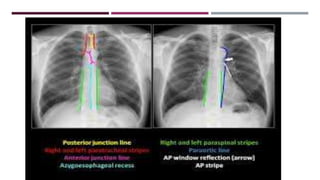

JUNCTION LINES

POSTERIOR JUNCTION LINE

ANTERIOR JUNCTION LINE

AZYGO-OESOPHAGEAL INTERFACE

PLEURO-OESOPHAGEAL STRIPE

PARASPINAL LINE